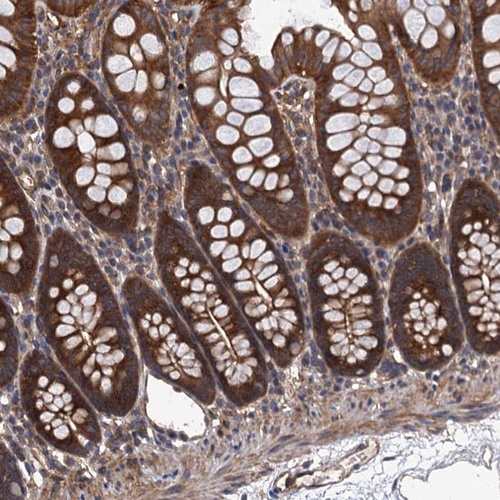

Immunohistochemical staining of human colon shows strong cytoplasmic positivity in glandular cells.